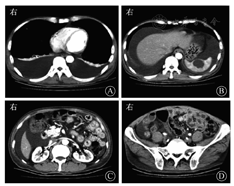

粪便隐血试验阳性。3次粪便培养均阴性。肝功能:白蛋白为15 g/L,总蛋白为34 g/L,ALT、AST、胆红素等均正常。肿瘤标志物:CA125为87.51 kU/L,AFP、CEA、CA19-9均正常。甲状腺功能:总三碘甲状腺原氨酸(total triiodothyronine,TT3)、总甲状腺素(total thyroxine,TT4)、游离三碘甲状腺原氨酸(free triiodothyronine,FT3)、游离甲状腺素(free thyroxine,FT4)均轻度降低,促甲状腺素(thyroid stimulating hormone,TSH)正常。PPD试验阴性,血清及腹水结核感染T细胞斑点试验(T-SPOT)阴性,腹水呈乳糜性,腹水结核PCR阴性,腹水细胞病理未查见癌细胞。血常规、尿常规、肾功能、24 h尿蛋白定量、离子5项(钾、钠、氯、总钙、二氧化碳)、心电图、心脏多普勒超声检查、自身抗体系列、ESR、门静脉系统血管多普勒超声检查均未见明显异常。腹部超声检查:①腹盆腔积液(中至大量);②脾囊肿可能,肝、胆、胰、双肾、膀胱、输尿管、前列腺均未见明显异常;③腹膜无增厚。胸腹部增强CT(图2):①肠系膜见大小不等的多个肿大淋巴结,最大者长径约2.4 cm,中腹部局部肠管增厚,淋巴瘤?不除外IBD,建议结合肠镜检查;结肠扩张积气,腹盆腔积液,睾丸鞘膜积液。②肝右叶近肝顶有小条索状低密度影,多系局部肝内胆管扩张;脾上极囊性低密度灶,考虑良性病变,脾内囊肿可能;胆囊炎,胆囊窝及腹膜后有稍肿大淋巴结。③双侧胸腔积液并双肺下叶膨胀不全,右肺中叶及左肺上叶舌段有少许渗出。

放射科杨勇副主任医师:患者腹部CT提示,肠系膜见大小不等多个肿大淋巴结,最大者长径约2.4 cm,中腹部局部肠管增厚,淋巴瘤?不除外IBD,建议结合肠镜检查。结肠扩张积气,腹盆腔积液。睾丸鞘膜积液。肝右叶近肝顶有小条索状低密度影,多系局部肝内胆管扩张;脾上极囊性低密度灶考虑良性病变,脾内囊肿可能;胆囊炎;胆囊窝及腹膜后稍肿大淋巴结。双侧胸腔积液并双肺下叶膨胀不全,右肺中叶及左肺上叶舌段有少许渗出。根据CT与患者症状和体征表现,①肠系膜淋巴结结核:患者血清T-SPOT及腹水T-SPOT检查均为阴性,暂不考虑此诊断。②肠系膜淋巴瘤:需结合患者小肠镜等检查进一步排查。③ IBD:可因慢性炎性反应出现肠系膜淋巴结炎性反应性增生,亦需结合内镜进行诊断。